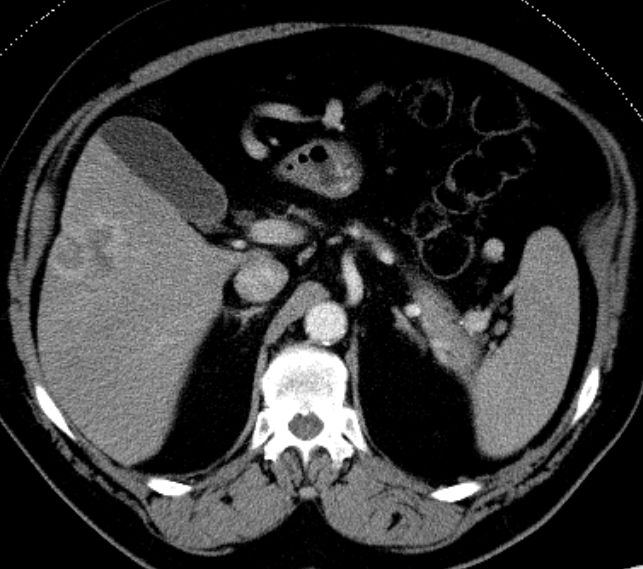

| Diagnostik | 70-jähriger Mann mit unklaren Oberbauchbeschwerden rechts. Klinisch vergrößerte Leber tastbar. Metastasen in BWK 8, Lunge und abdominalen sowie mediastinalen Lymphknoten. Leberbiopsie: Invasives Adenokarzinom, intrahepatisches Cholangiokarzinom. Das CT zeigt eine über 10 cm große Raumforderung im rechten Leberlappen. ![]() |